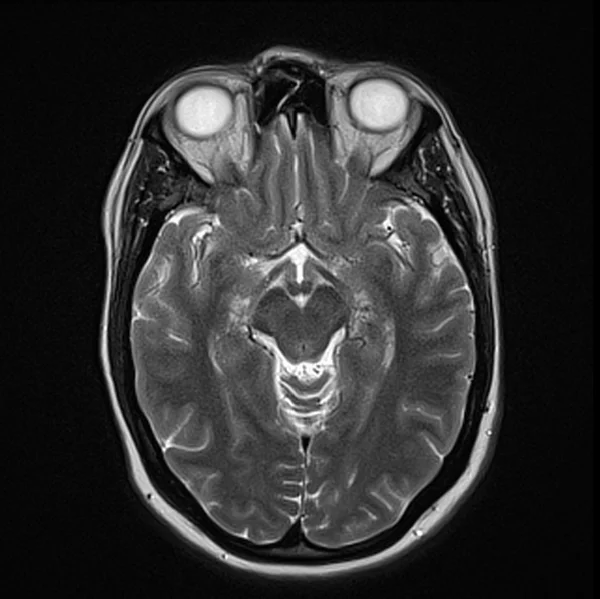

Brain MRI T2 axial images